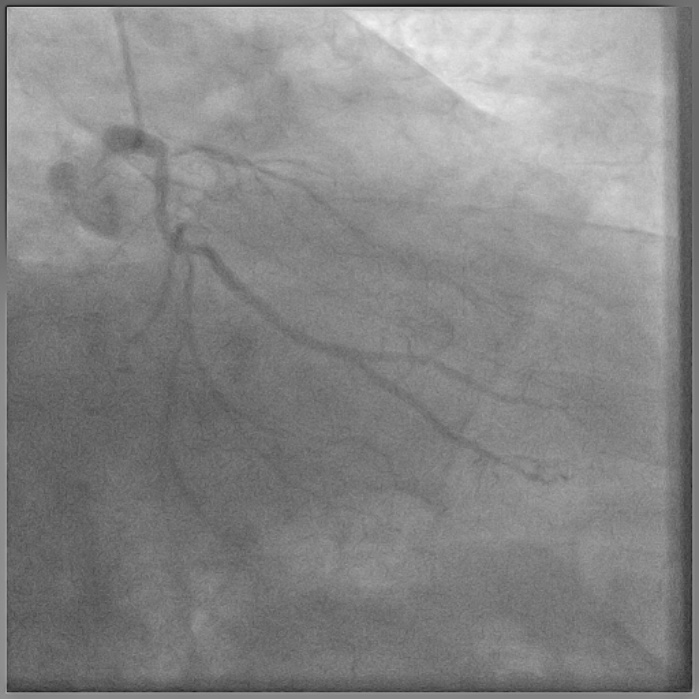

8F JL coronary guide catheter was taken from the right femoral artery and a TIG diagnostic catheter was taken from right radial artery and bilateral angiograms were taken. A floppy guide wire was placed in Lcx and ostial Lcx lesion was predicated with a 2*12 mm non compliant balloon. An IVUS catheter was placed over Lcx wire and under IVUS guidance a Gaia 3 coronary wire (Asahi, Japan) over a micro catheter was used to probe the ambiguous osmium of LAD (T1). Using contralateral injection in RCA, the Gaia 3 wire was seen extending into the false lumen in distal LAD. A Conquest Pro 12 (Asahi, Japan) was then taken over a micro catheter using a parallel wire strategy and successfully negotiated in distal true lumen of LAD (T2). After pre dilatation of LAD, Conquest Pro wire was exchanged for a floppy guide wire over a micro-catheter. IVUS run was then taken from LAD to LM and LCx to LM for vessel sizing. In view of the discrepancy in size of LAD/LCx and LM, 2 coronary stents were placed in a V technique from LM to LAD and LM to LCx and deployed. The stents were then post dilated and final kissing balloon inflation was done and the results were optimised by IVUS. Final cine showed well expanded LM LAD/LCx stents with TIMI 3 flow (T3).

Case Summary